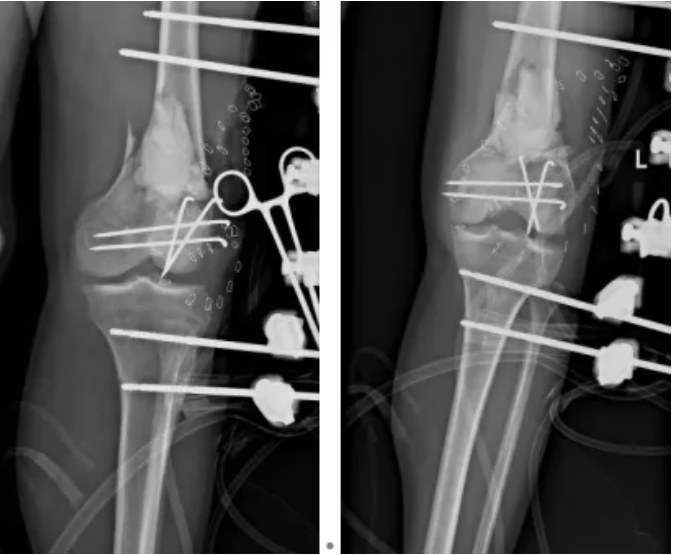

“生命至上” 是救治的核心原則。醫(yī)院立即啟動多學(xué)科協(xié)作機(jī)制,骨科牽頭聯(lián)動影像科、重癥監(jiān)護(hù)室、心胸血管外科、麻醉手術(shù)科等多科室,快速制定個體化分期治療方案。到院當(dāng)晚,急診手術(shù)率先開展:對左膝部開放性傷口徹底清創(chuàng),因骨質(zhì)缺損多且污染嚴(yán)重,術(shù)中創(chuàng)新性使用抗生素骨水泥填充缺損區(qū)域,同時以外固定架臨時固定左下肢,并行右脛骨骨牽引術(shù)。

8月26日,實(shí)施開放性左股骨遠(yuǎn)端粉碎性骨折壞死組織切除性清創(chuàng)術(shù),取出原有內(nèi)固定物,采用萬古霉素抗生素骨水泥鋼板內(nèi)固定術(shù),徹底穩(wěn)固骨折部位。